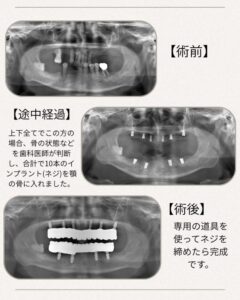

オールオンインプラントは、インプラントで全ての歯を固定する治療です。

• 骨が少なくても対応できる場合がある

• 手術回数が少ない

• 即日仮歯が入ることが多い(即時負荷)